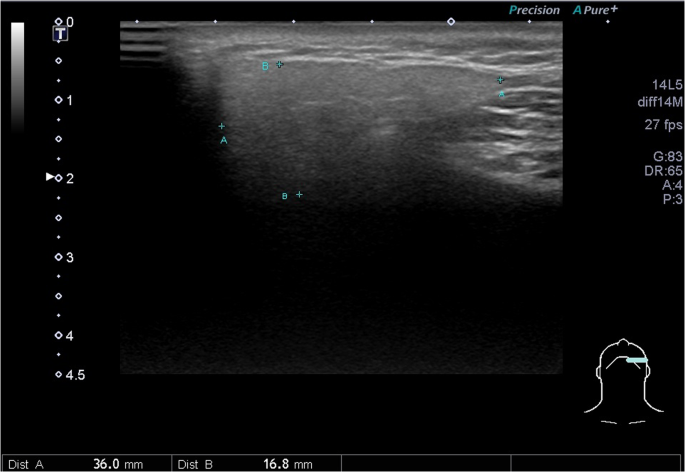

This study protocol was approved by the Far Eastern Memorial Research Ethics Review Committee (IRB No: 104180-E). The study was conducted in accordance with relevant guidelines and regulations. Informed consents were obtained from all participants. The sonograms were performed by L.J.,Liao (with experience of more than 10,000 ultrasound procedures), who was blind to the included cases, using a Toshiba Apolio 500 platform (Otawara, Japan) with a high-resolution 5-MHz to 14-MHz real-time linear-array transducer. All methods performed were in accordance with the manufacturer’s relevant guidelines and institutional regulations. We measured three dimensions of each submandibular (Fig. 1.) and parotid gland, including the dimensions of anterior-posterior length and paramandibular depths in the transverse axis and the dimensions of cranio-caudal height, as described in previous literature7,8,9. The ROI (region of interest, about 5 mm in circle) over the central part of the parotid and submandibular glands were recorded with mean SWV (Fig. 2.). From January 2016 to March 2018, a recruitment announcement for clinical trial was posted in our outpatient department of FEMH. Healthy adults (age ≧ 20) without cancer or major disease history, acute viral or bacterial inflammation were recruited as participants of this study, and were invited to receive salivary glands ultrasound measurements. During the period, we also collected data from patients who were referred from our hospital to our ultrasound center for head and neck examination. Subjects with head and neck cancer were included as part of the post-radiation group. We excluded patients without prior radiotherapy to the neck, or patients with ongoing radiotherapy or residual tumor. The radiotherapy of these patients was conducted in our hospital which consisted of three techniques: TOMO (Helical Tomotherapy), VMAT (Volumetric Modulated Arc Therapy) and IMRT (Intensity Modulation Radiation Therapy).We measured their body weight and body height before US examination. We also recorded the patients’ histories of diabetes, hyperlipidemia and hypertension according to their medical records.

For 100 parotid and submandibular glands, the median dimensions and SWV are shown in Table 2. The median of the parotid glands measured 36.15 (IQR: 12.45) mm in the anterior-posterior median length. The median paramandibular depth dimension of the parotid parenchyma measured 16.95 (4.00) mm in the transverse section, and the cranio-caudal height measured 43.60 (10.10) mm. In the submandibular glands, we found an anterior-posterior length of 34.55 (IQR: 6.95) mm, a median depth of 16.60 (3.85) mm and a cranio-caudal height of 23.40 (15.30) mm. Further analysis revealed that the dimensions of the parotid and submandibular glands were related to the gender and BW (Tables 3 and 4). For parotid paramandibular depth, non-smokers (17.15 versus 13.00 mm, p < 0.01) had a larger dimension than that in smokers. Otherwise, the dimensions did not differ with age, hypertension or hyperlipidemia.